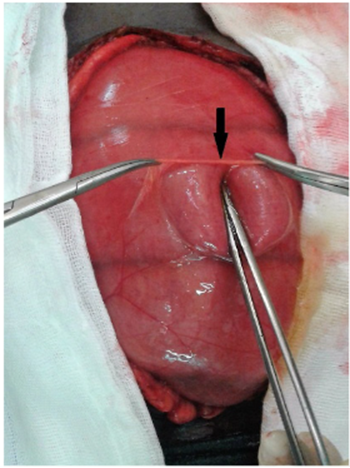

Se intervino quirúrgicamente de urgencia, identificándose gran distensión del intestino delgado desde el ligamento de Treitz hasta el íleon terminal, con una hernia paraduodenal izquierda como etiología de la obstrucción intestinal (Figura 2). Se hizo reducción del intestino delgado herniado y cierre del orificio herniario con sutura continua no absorbible (Figura 3). La evolución del paciente fue favorable.